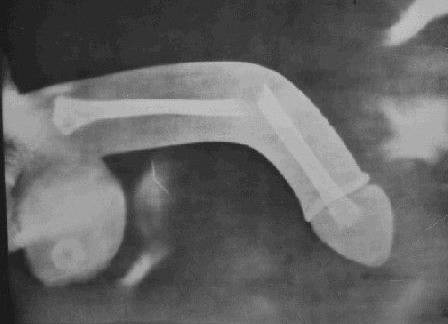

小伙再也不管羞不羞了,紧急赶到医院就诊。经诊断,小伙海绵体白膜断裂,不仅出现了一个普通鸡蛋般大小的血肿,还出现了弯曲。

2月23日,医务人员为小伙子进行了海绵体白膜修复术。手术过程中,医务人员从血肿内取出了已经发黑、变硬的血块。

经过紧张的手术过后,小伙子上的血肿被顺利清除,白膜裂口已修复,外观恢复正常。